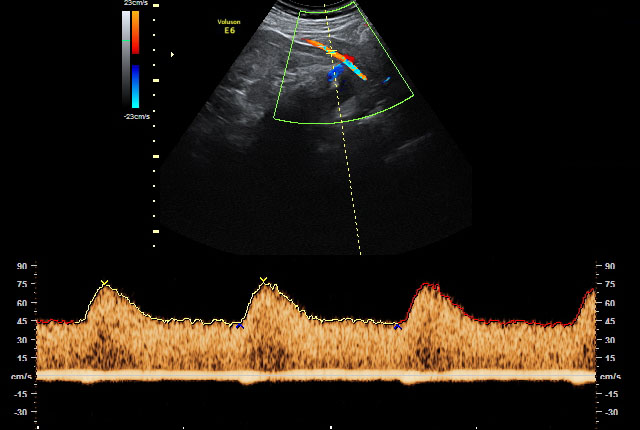

Wenn der Verdacht auf fetale Wachstumsstörungen und/oder fetale Fehlbildungen besteht, wird die Versorgungssituation des Ungeborenen durch eine spezielle dopplersonografische Untersuchung überwacht und die Funktion der Plazenta überprüft. Wir setzen hierbei den hochauflösenden Farbdoppler, also die sogenannte farbkodierte Doppler-Sonografie ein.

Bei der farbkodierten Doppler-Sonografie, einer bestimmten Form der Ultraschalluntersuchung, wird die Richtung des Blutflusses farblich dargestellt, um den Blutfluss in Arterien von dem in Venen unterscheiden zu können. Damit können auch Aussagen über das Ausmaß eventuell vorhandener Durchblutungsstörungen getroffen werden.